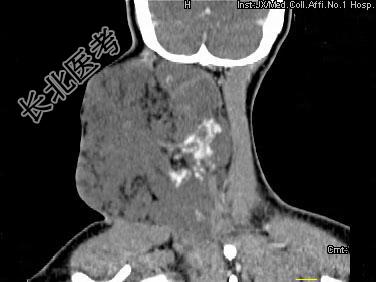

- 单项选择题女,32岁, 颈部包块8年余,包块逐渐长大, CT如图所示,最可能的诊断为 ( )

A、颈部神经纤维瘤

B、颈部横纹肌肉瘤

C、颈部巨大血管瘤

D、颈部神经鞘瘤

E、颈部异位甲状腺